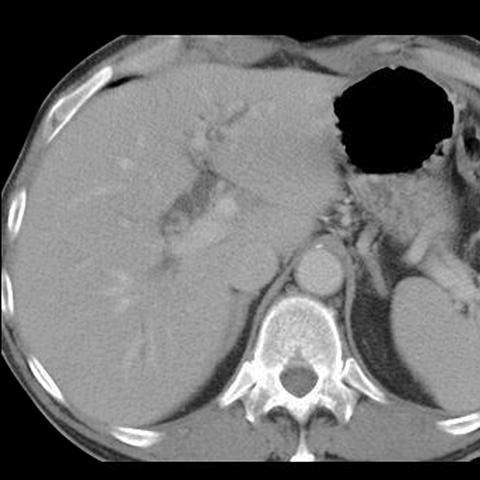

65-year-old male presents with painless jaundice. [1 of 5]